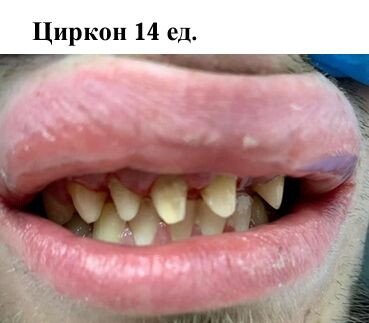

Фотогалерея